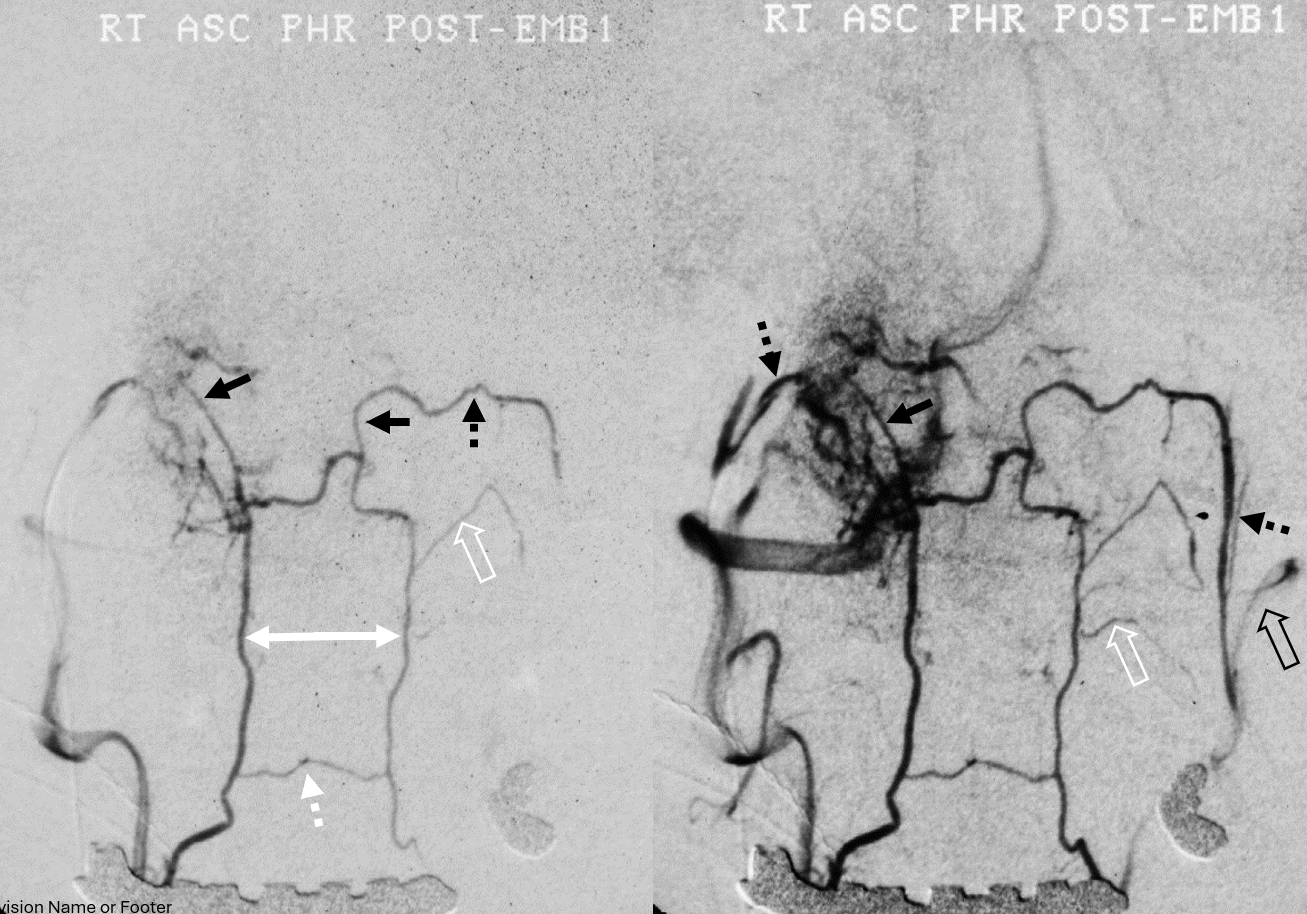

Vintage analog subtraction angio of the same. Microcatheter in the right proximal odontoid arcade, refluxing into right vert in earlier phase left image, and in later phase via retrograde opacification of the left odontoid arcade spilling contrast into the left vert (open black arrow). Both C1 epidural connections (black arrows) to the hypoglossal divisions (dashed black arrows), and in later phase further retrograde opacification of bilateral pharyngeal trunks — no arrows, figure it out yourself. There are ventral epidural anastomoses at C2 body (dashed white arrow) and C2 longitudinal segmental dural / radiculodural arteries (open white arrows). In the later